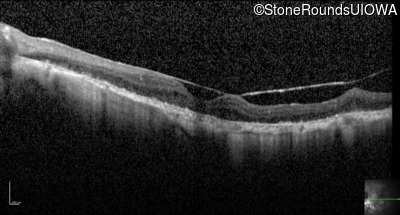

Optical Coherence Tomography - Left - 20/50 -2

Exemplar / OCT Stack

OCT Stack